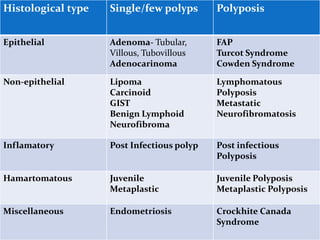

This document discusses colorectal polyps. It defines polyps and describes their types, including neoplastic and non-neoplastic polyps. It discusses adenomatous polyps in depth, noting their malignant potential increases with size over 1cm and villous architecture. Radiological diagnostic methods for polyps including single and double contrast barium enema and CT colonography are explained. The document provides an overview of polyp pathogenesis and genetic syndromes like FAP that increase cancer risk.